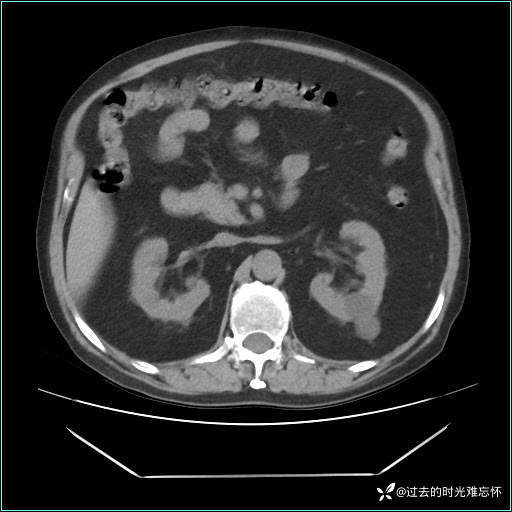

男子肚子大如孕晚期,一看腹腔竟被脂肪填满了...

患者男,71 岁,因「反复腹痛腹胀 1 月」入院。

现病史:患者 1 月前无明显诱因下出现腹痛腹胀症状,腹痛呈隐痛,当时未予以重视,后症状有所加重,常在进食辛辣刺激油腻等食物后出现腹痛,口服药物治疗症状能得到控制,病情控制一般。现为求诊治来我院,拟“腹痛”入院。病程中患者神志清楚,精神一般,无咳嗽咳痰,无恶心呕吐,近期体重无明显变化。